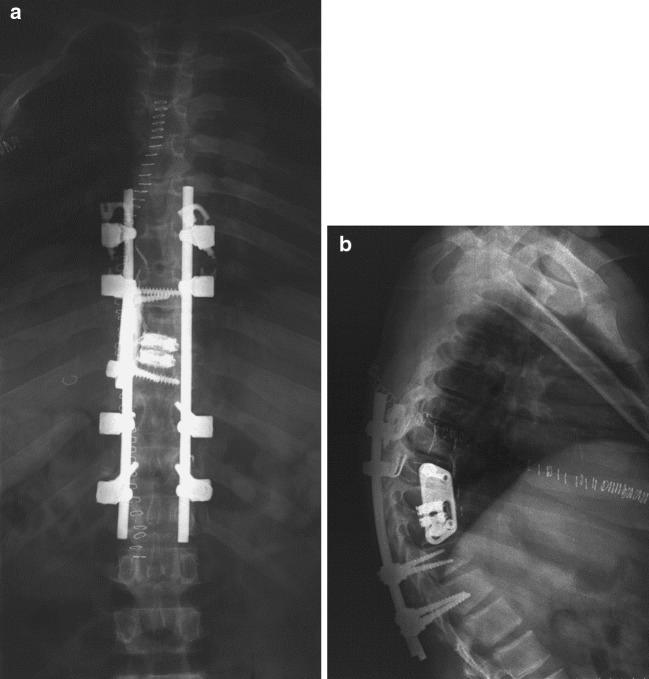

We present the case of a 14-year-old male with Scheuermann's disease and significant neurological deficit due to thoracic disk herniation at the apex of kyphosis. He was treated with an anterior decompression, anterior and posterior fusion in the same setting using plate, cage and a segmental instrumentation system. The patient had an excellent outcome with complete neurological recovery.

我们报告一例14岁男性,患有休曼病,因脊柱后凸顶点处的胸椎间盘突出而出现明显神经功能缺损。他接受了前路减压,并在同一手术中使用钢板、椎间融合器和节段性内固定系统进行了前路和后路融合。患者神经功能完全恢复,预后良好。